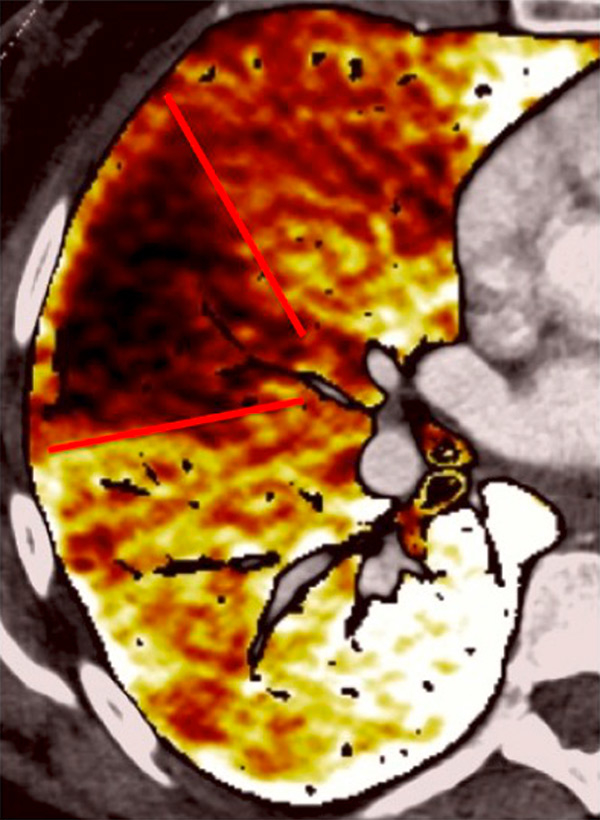

Nowadays, DECT imaging can be used for pathologies other than CTEPH and seems to offer advantages for PH characterisation because different DECT findings have been described in acute pulmonary embolism, CTEPH and idiopathic PAH (IPAH). In fact, perfusion defects are smaller and less defined in PAH than in CTEPH. This is likely due to focal under- and overperfusion as a result of the structural pulmonary vascular changes that occur in PH, which include vascular endothelial damage, cellular proliferation and occlusion in the distal pulmonary vasculature. Perfusion heterogeneities in DECT imaging are also common and seen in most cases of PAH. Findings of perfusion inhomogeneities related PAH have long been recognised in scintigraphy, and often are referred to as having a “mottled” pattern [42]. These perfusion defects are different from those seen in CTEPH, with nonsegmental and poorly defined defects (fig. 5). This heterogeneity is related to the severity of the disease. In PAH, this perfusion variability on scintigraphy is well correlated with pulmonary vascular resistance, as Talwar et al. showed [43]. Recently, similar results were published for DECT techniques (fig. 6). Ameli-Renani et al. described an increased enhancement of pulmonary arteries with reduced iodine lung perfusion in PH, and a good correlation of DECT perfusion heterogeneities with pulmonary vascular resistance; they showed a greater heterogeneity in parenchymal iodine maps in PH without pulmonary embolism [13]. The authors concluded that perfusion heterogeneities seen in DECT appear to be a direct reflection of pulmonary vascular resistance.

Figure 6

Perfusion heterogeneities in idiopathic pulmonary artery hypertension (stars) in two different patients (A/B). The dilatation of the arteries in pulmonary hypertension (arrows) is not always observed depending on the severity of pulmonary hypertension.